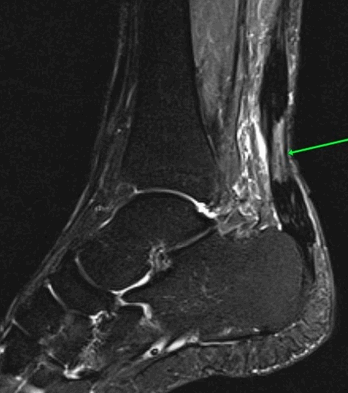

МРТ тазобедренных суставов.

МР-признаки базисцервикального перелома шейки правой бедренной кости с наличием зон инфаркта головки и шейки правой бедренной кости, синовита правого тазобедренного сустава, отека окружающих мягких тканей справа.